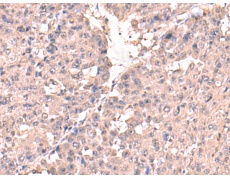

IHC positive control: |

Human liver cancer |

IHC Recommend dilution: |

50-300 |